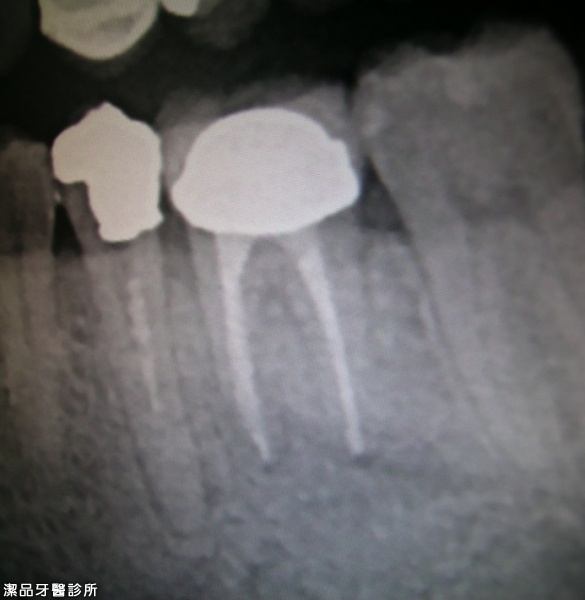

根管重新治療案例-002

案例簡述:

根管重新治療

三個月後